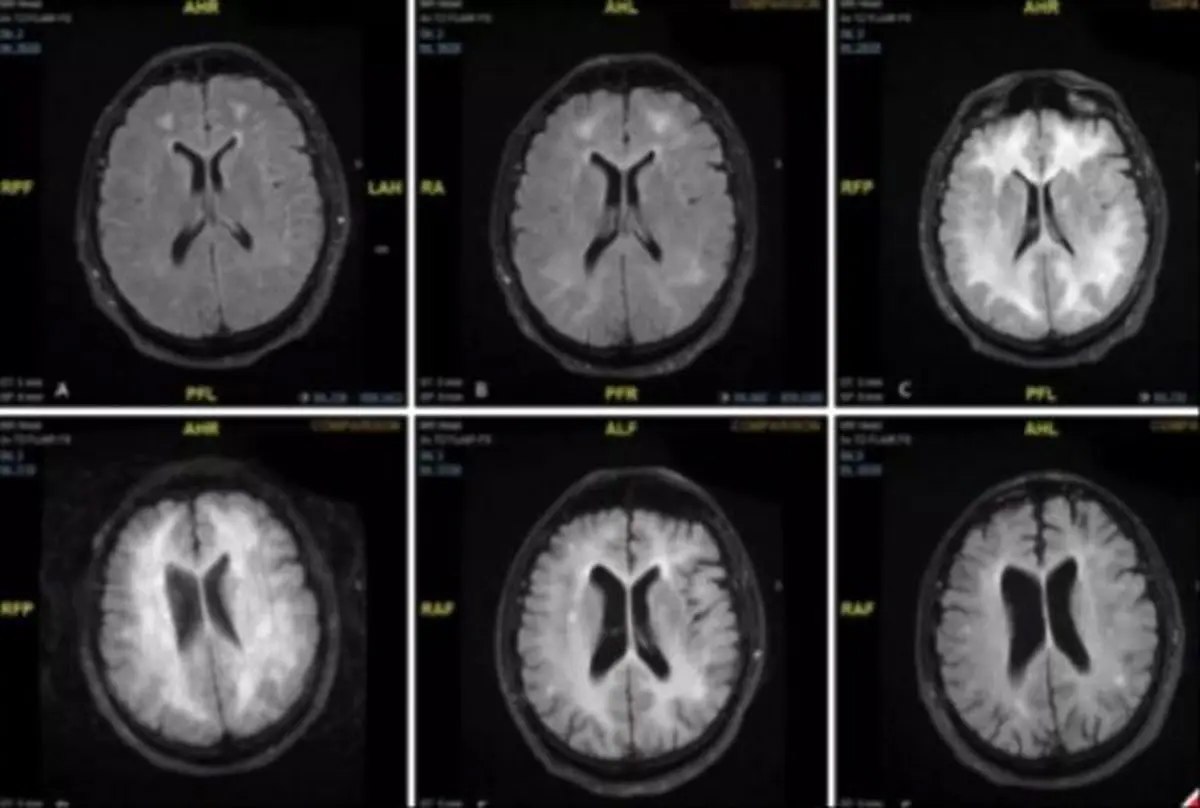

اسکن‌های مغزی نشان می‌دهد که چگونه کوکائین می‌تواند مغز را تحلیل برده، سلولها را اندک‌اندک محو کند و در نهایت منجر به معلولیت یا مرگ مصرف‌کننده شود. بیماری که از او اسکن گرفته شده بود، از عوارض جانبی نادر اما شدید مصرف کوکائین به نام لکووانسفالوپاتی سمی ناشی از کوکائین رنج می‌برد.

در این اسکن مغزی مشخص شد که ماده سفید موجود در مغز وی آسیب دیده بود که منجر به تشخیص آنها شد. وی علائمی مثل تغییر سطح هوشیاری، گیجی، اختلال در زبان، تغییر بینش، تب یا اسپاسم را از خود نشان می‌داد.اکنون بیمار پس از درمان گسترده‌ای از جمله استروئیدها، آنتی‌بادی‌ها و تبادل پلاسما، به یک مرکز توانبخشی اعزام شده است و کمی بهبود یافته است."